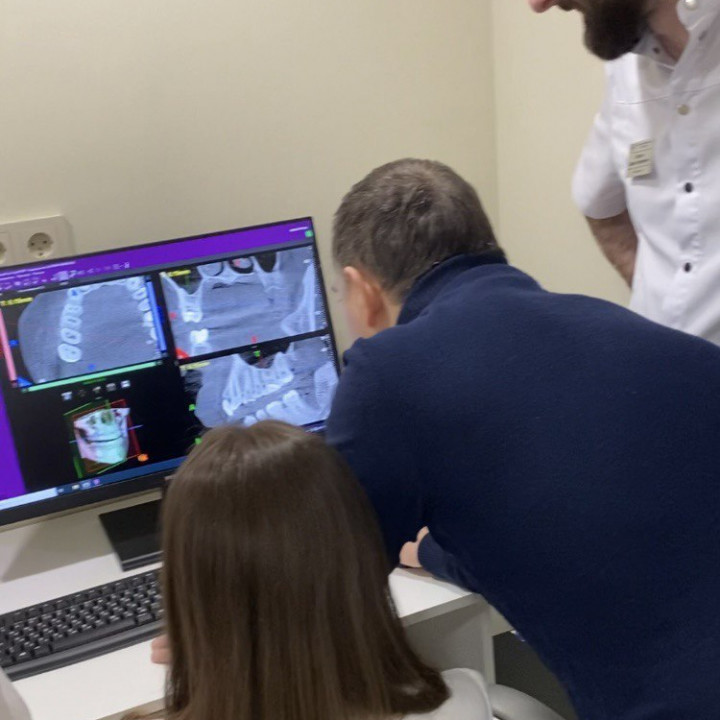

При КТ-обследовании трехмерный снимок на экране компьютера возникает в результате объединения большого количества послойных двухмерных снимков в единое целое, что становится возможным благодаря сложному программному обеспечению. Этот метод гораздо информативней традиционной двухмерной плоской рентгенографии зубов и позволяет нашим специалистам максимально эффективно ставить диагноз и проводить лечение.